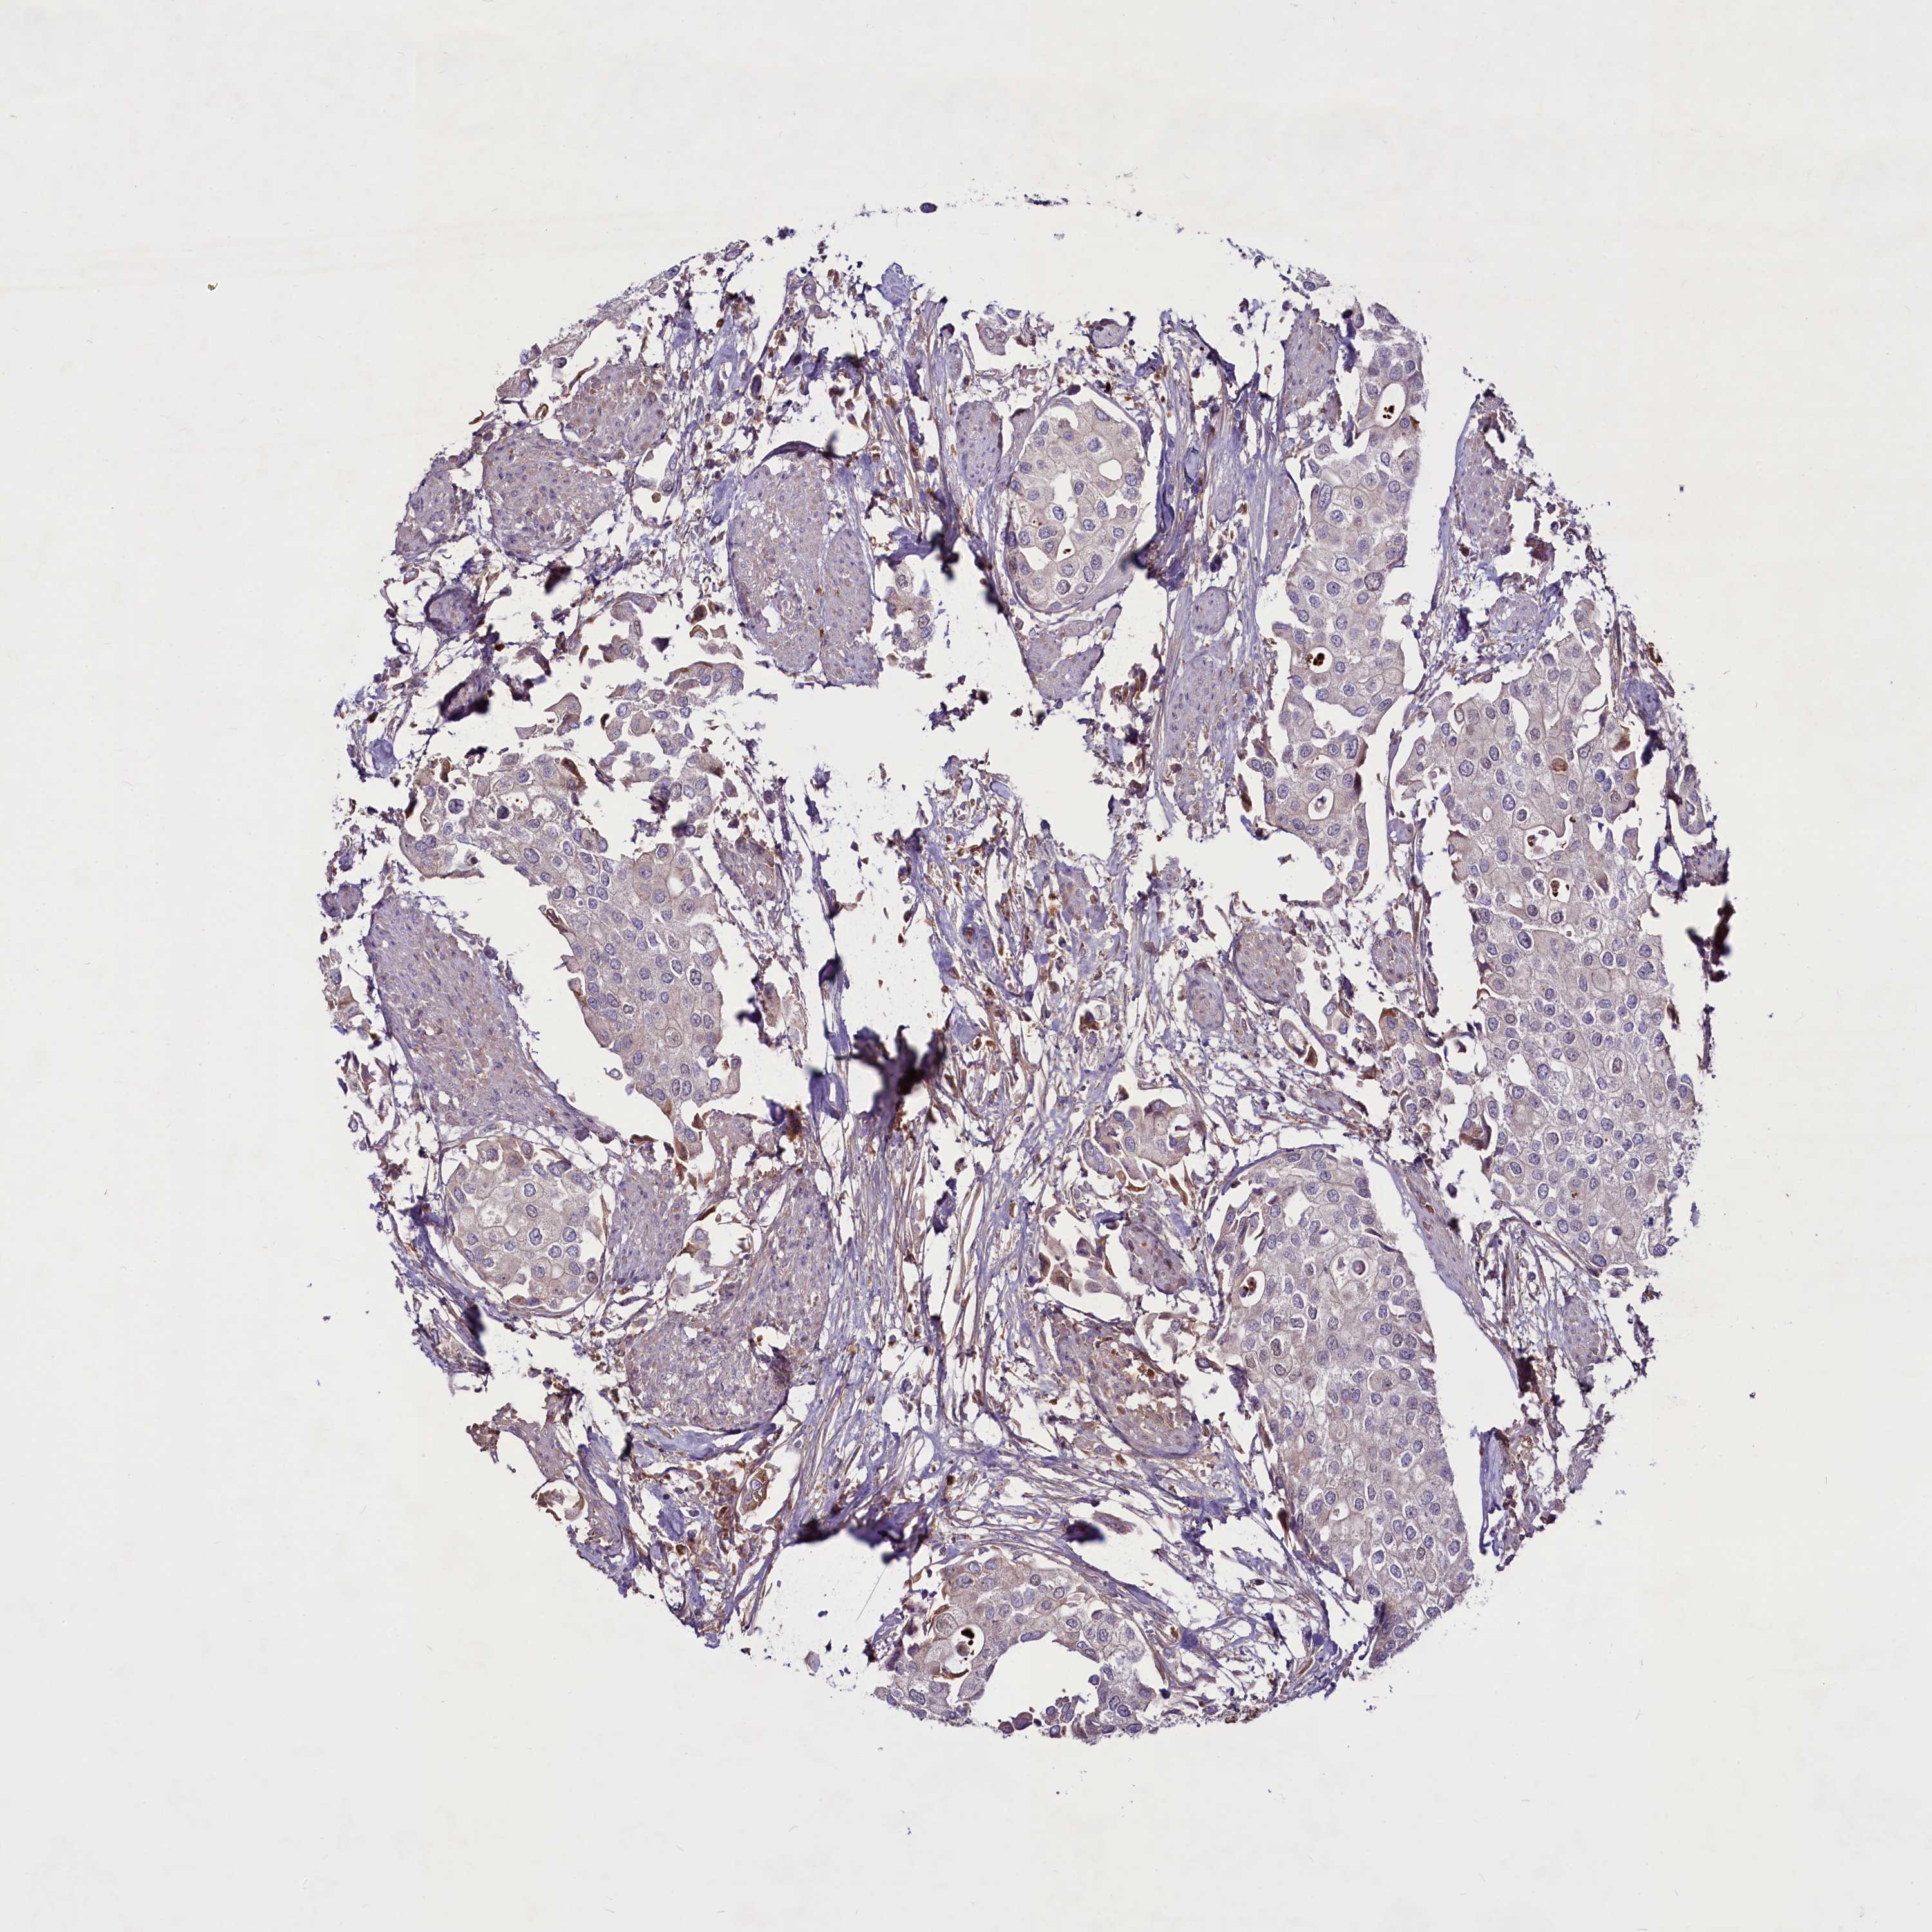

UROTHELIAL CANCER - Protein expressioni

A mouse-over function shows sample information and annotation data. Click on an image to view it in a full screen mode. Samples can be filtered based on level of antibody staining by selecting one or several of the following categories: high, medium, low and not detected. The assay and annotation is described here.

Antibody stainingi

Antibody staining in the annotated cell types in the current human tissue is reported as not detected, low, medium, or high, based on conventional immunohistochemistry profiling in selected tissues. This score is based on the combination of the staining intensity and fraction of stained cells.

Each image is clickable and will lead to virtual microscopy that enables deeper exploration of all samples and also displays staining intensity scores, fraction scores and subcellular localization as well as patient and tissue information for each sample.

Antibody HPA042124

Antibody HPA049484

Staining

High

Medium

Low

Not detected

Intensity

Strong

Moderate

Weak

Negative

Quantity

>75%

75%-25%

<25%

None

Location

Nuclear

Cytoplasmic/membranous

Cytoplasmic/membranous,nuclear

Urothelial carcinoma, High grade

Urothelial carcinoma, Low grade